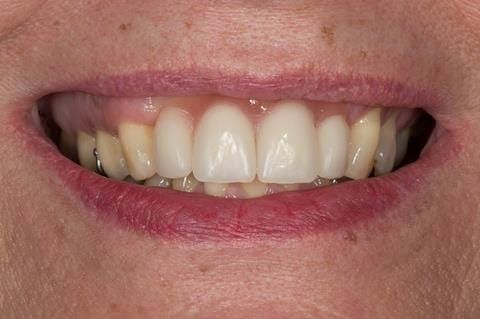

- High smile line showing gum above gingival zeniths of upper front teeth when smiling. Aesthetic failure of the upper four incisors with inflammation of the gingivae and mis-match of the gingival zenith levels.

- Extract the upper 2-2 teeth and replace with an interim acrylic based partial denture. Reline the interim denture over 9 - 12 months, replacing with a definitive cobalt chromium based partial denture. The definitive denture would ideally be designed as an occlusal protective splint to reduce the the potential for mechanical wear and breakages of the moderately/heavily restored maxillary dentition. In addition, should further upper teeth require extraction they could be added on to the denture cobalt chromium framework - therefore a new prosthesis would not be required as future teeth are lost. This option would produce an excellent aesthetic outcome. This is the option the patient chose to have.

Following consultation and second discussion appointment the patient chose to have option 3 namely, a maxillary cobalt chromium based partial denture/protective occlusal splint. The clinical situation and treatment process is shown in detail below with photographs. The patient was successfully rehabilitated with this and her quality of life considerably improved. The clinical work was provided by Finlay and the technical work by Rowan.